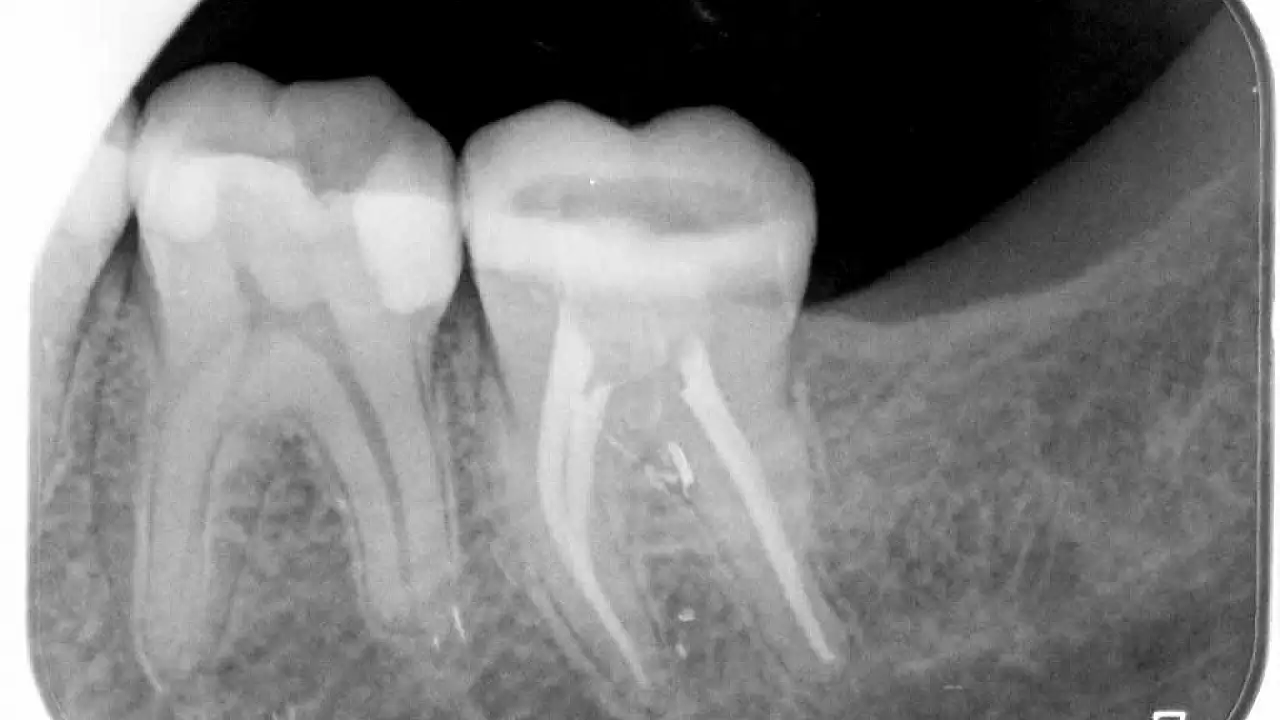

Dijital Görüntüleme - Fosfor Plak

Kliniğimizde tüm tedaviler sırasında, dişinizin anlık görüntüsünü sağlamak için dijital röntgen ile görüntüleme yapılabilmektedir. Bu görüntüleme ile gerekli bilgiler beklemeye gerek olmadan bilgisayar ekranında anında elde edilebilir. Bu görüntüleme teknolojisi bilgisayar üzerinde değişiklik yapmaya izin verdiği için geleneksel filmlere kıyasla daha doğru teşhis ve tedaviyi mümkün kılar. Filmler kolaylıkla ve bozulmadan depolanabilir. İnce ve ağız yapılarının şeklini alabilmesi sayesinde kullanım sırasında üstün bir konfor. Ayrıca bu filmler ile geleneksel filmlere göre maruz kalınan radyasyon dozu önemli ölçüde azalmaktadır.